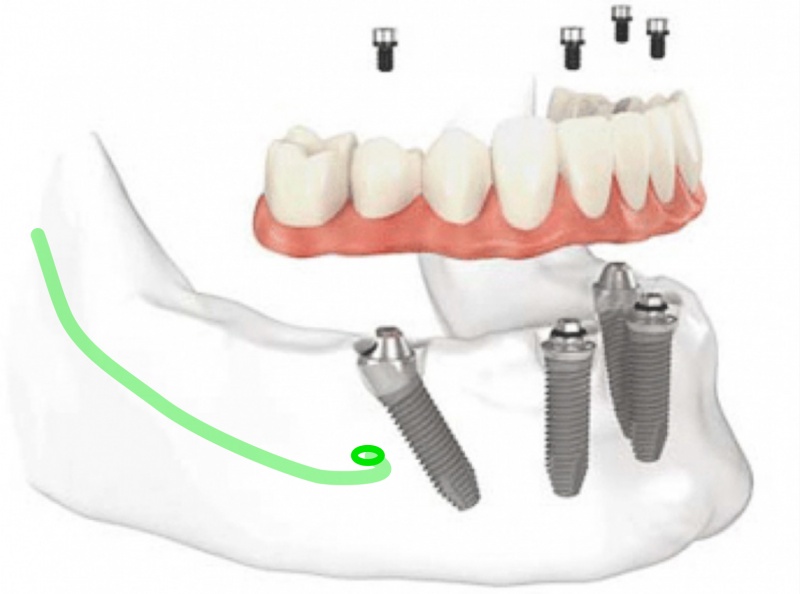

De onderkaak is ideaal voor implantaten en vaste tanden. Bijna elke onderkaak is geschikt voor een onmiddellijke belading van de implantaten.De procedure is eenvoudig, duidelijk en snel te realiseren. In de bovenkaak is de grootste zorg van de chirurg om allesjuist uit te kiemen naar esthetiek en fonetiek toe, maar in de onderkaak ligt de focus meer op rechtstreeks comfort. De onderkaak reabilitatie is veel eerder functioneel en recht aan recht uit.

Waarom worden implantaten in de onderkaak vaak langs voor geplaatst?

Dit is waarschijnlijk de meest essentiële overweging die we tijdens de planning dienen te maken. Indien de onderkaak zijn tanden verliest, dan resorbeert de kaak door rechtstreekse druk van het kauwen en de continue wrijvingen van de uitneembare prothese. In de onderkaak maken we steeds onderscheid tussen het gebied voor de alveolaire zenuw en het gebied erachter. Vooraan heeft de gevoelszenuw reeds de kaak verlaten en loopt die verder in de lip. Deze zenuw zorgt voor gevoel in de onderlip en beschadiging ervan is storend en dient vermeden. Praktisch gezien worden de implantaten geplaatst vooraan in de kaak en vòòr de zenuwuitgang, en meestal slechts uitzonderlijk meer achteraan.